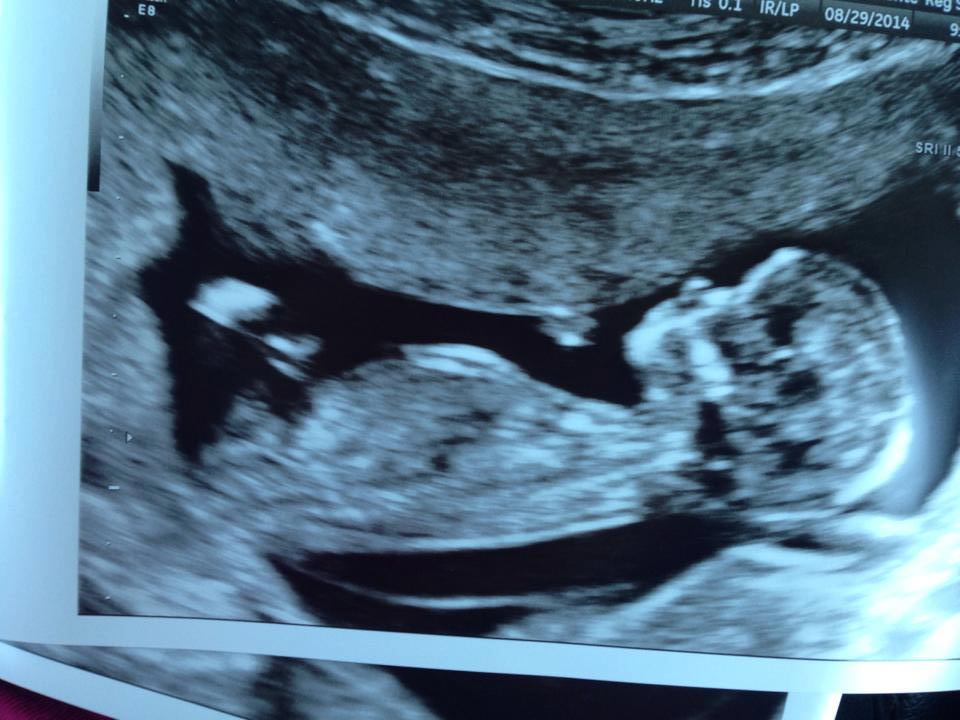

She's 12w2d and had an unexpected US today - she is having her NT scan tomorrow so hopefully gets much better pics but figured if we can post these here today why not? Any guesses??? THANKS!

Attachment 20655